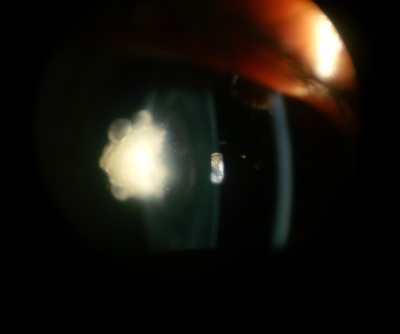

Posterior Subcapsular Cataract

Etiology

Posterior subcapsular cataracts (PSC) are opacities located in the most posterior cortical layer, directly under the lens capsule. This type of cataract tends to occur in younger patients compared to cortical or nuclear sclerotic cataracts. Progression is variable but tends to occur more rapidly than in nuclear sclerosis. Thus, PSC can reduce visual acuity earlier and quicker than its more common nuclear or cortical cataract counterparts. Equatorial and posterior cortical degeneration during PSC formation leads to posterior migration, inward displacement, and equatorial lens epithelial cell (LEC) malformations. During this aberrant migration of equatorial LECs to the posterior pole, many cells take on a characteristic ballooned or swollen bladder-like shape, first described by pathologist Carl Wedl. Accumulation of these dysplastic, nucleated, bladder cells, or Wedl cells, begins as a focal dot-like area in the posterior cortex, proceeding into granular opacities in the posterior pupillary zone of the lens, and in advanced cases, ultimately growing denser into a large, white, granular, vacuolar plaque. On slit-lamp examination, these opacified, granular plaques can appear similarly to posteriorly migrating Elschnig pearl formations postcataract. Histologically, Wedl cells are described by their scarce organelles, crystalline proteins, prominent cytoskeleton, and degenerating nuclei.

The exact mechanisms behind the pathologic migration or Wedl cell generation are not fully understood, although ionic uncoupling pathways, oxidative stress, and interleukin-induced LEC activation have all been suggested to play a role in pathogenesis. Risk factors for PSC and Wedl cell pathology include but are not limited to calcium imbalance, atopy, ionizing radiation, high or prolonged use of glucocorticoids, diabetes, myopia, ocular inflammation (uveitis), and vitrectomy. These Wedl cell aggregations, a signature hallmark of all PSC development, cause decreased visual acuity and contrast sensitivity. Symptoms include glare and difficulty seeing in bright light, and near vision is often more affected than distance.